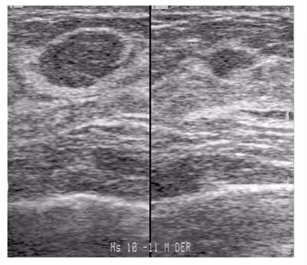

O diagnóstico inicial é feito pelo quadro clínico e ultrassonografia (USG), mas o definitivo só por exame histológico da lesão. Às vezes as bancas cobram a descrição da imagem: nódulo regular ou macrolobulado, hipoecoico, horizontal e sem sombra acústica posterior. Na interpretação do achado, é classificado como BI-RADS 3. Se não palpável, não se realiza a biópsia, somente controle clínico e radiológico a cada 6 meses, por 2 anos. Após estabilidade, o seguimento é anual. A exérese cirúrgica fica restrita nos casos de prejuízo estético/emocional, desejo da paciente ou se houver mudanças no crescimento.

Figura 1.2 - Fibroadenomas ao exame ultrassonográfico